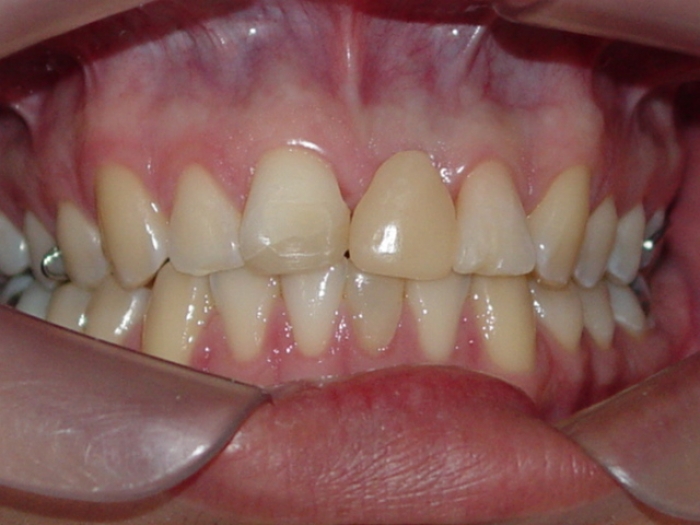

Imagem final do caso terminado em Agosto de 2013

Sorriso final